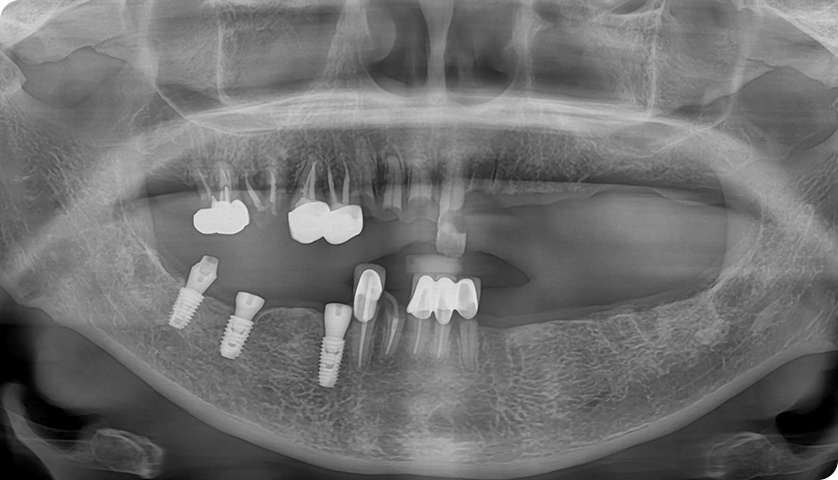

굿나잇치과의 자신있는

BEFORE & AFTER

임플란트

임시 임플란트

2024.04.23 - 2024.07.09

본 사진은 동일 환자의 치료 전후 사례로, 동의를 받아 촬영·게시하였으며,

치료 결과는 개인의 구강 상태에 따라 차이가 있을 수 있습니다.